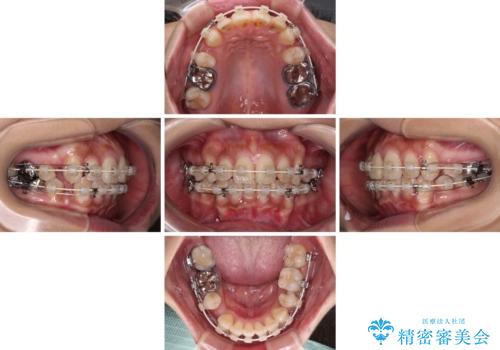

- 口元の閉じにくさを気にして来院された患者様です。

上下ともに歯列が前方に突出していたため、上下左右の第一小臼歯4本を抜去し、ワイヤー装置による矯正治療を行うこととしました。

舌の突出癖による影響もあったため、舌のトレーニングを並行して実施しました。

左下奥歯にむし歯が認められるため、矯正治療後にセラミックインレーにて修復治療を行うこととしました。

4本の歯を抜歯したことで、飛び出していた口元が引っ込み、横顔が大きく改善されました。